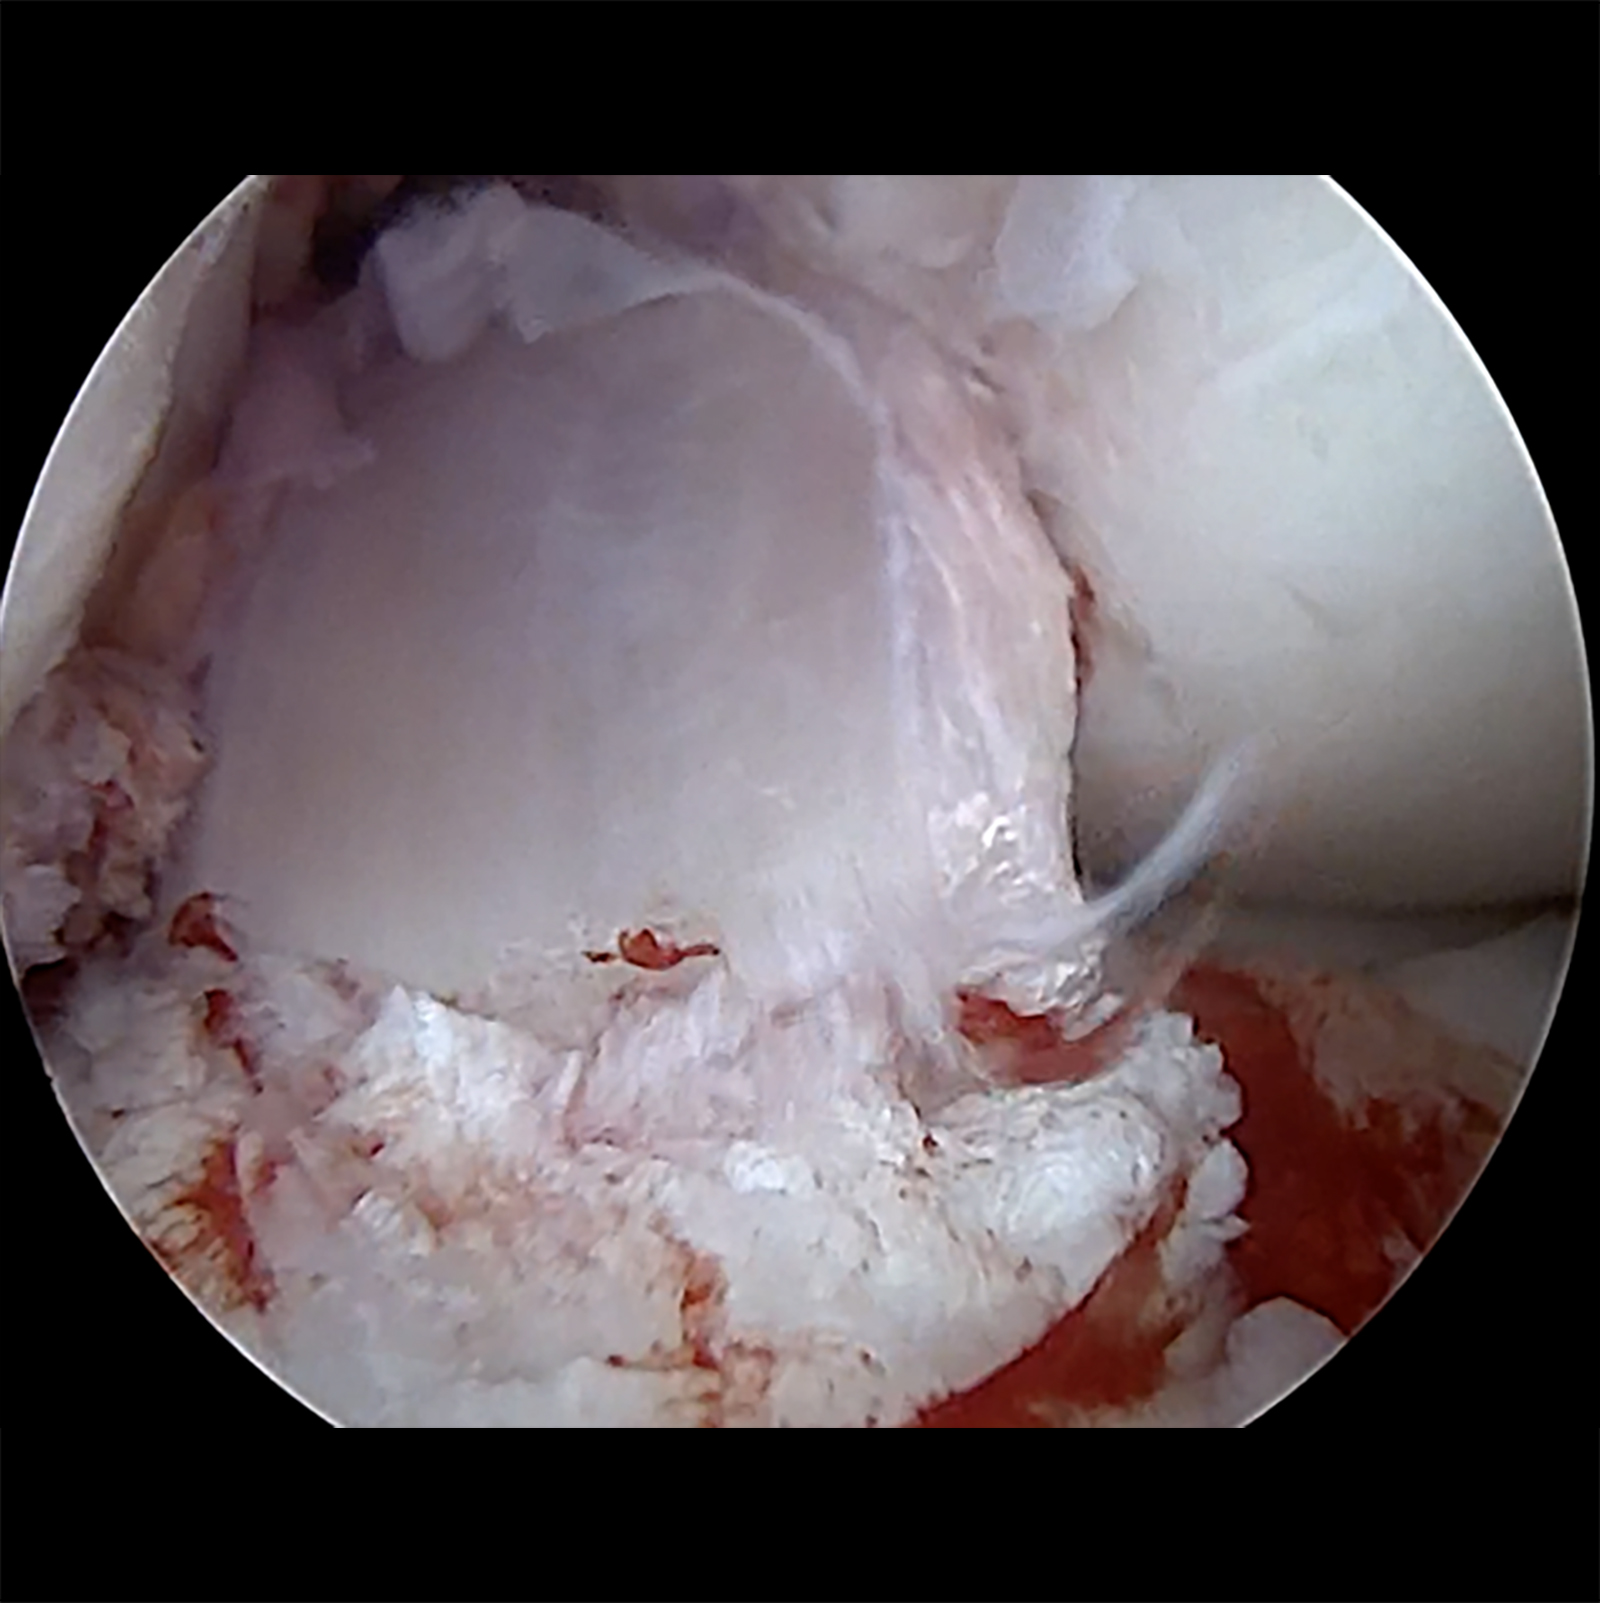

Primär zu differenzieren ist die anterolaterale und die anteromediale Kniegelenksstabilität (ALRI und AMRI), die Kombination ist mit Ausnahme von Multiligamentverletzungen eher selten. Die kombinierte anatomische Rekonstruktion des vorderen Kreuzbandes, der anterolateralen Kapsel-Band-Rekonstruktion (ALL-Plastik, Rekonstruktion nach Lemaire, Müller, Ellison, o. ä) und bei entsprechender Instabilität des posteromedialen Meniskus-Band-Komplexes stellen den derzeitigen Goldstandard dar, wobei kein wissenschaftlich klinischer Unterschied in den o. g. anterolateralen Rekonstruktionstechniken derzeit besteht. Eine vermehrte Belastung des lateralen Kompartimentes durch das additive Verfahren besteht nicht [24]. Die additive periphere Stabilisierung zur Vorderen Kreuzbandrekonstruktion führt zu einer signifikant geringeren VKB-Reinsuffizienz (von 10 – 15 % auf unter 5 %) und verbesserten Meniskuskonsolidierung, sodass in Zusammenschau mit der aktuellen Literatur zunehmend von einem „Must have“ der modernen Kreuzbandchirirgie gesprochen werden sollte [10 – 13]. Bei Vorliegen einer kombinierten anteromedialen Kniegelenksinstabilität ist die anteromediale Bandrekonstruktion additiv zur vorderen Kreuzbandrekonstruktion alternativlos, da die verbleibende AMRI obligat zu einem (zumeist atraumtischen frühen) Versagen der Kreuzbandplastik führt.

- „Save-the-meniscus“: Repair / Teilrepair der Meniskusstrukturen [25]